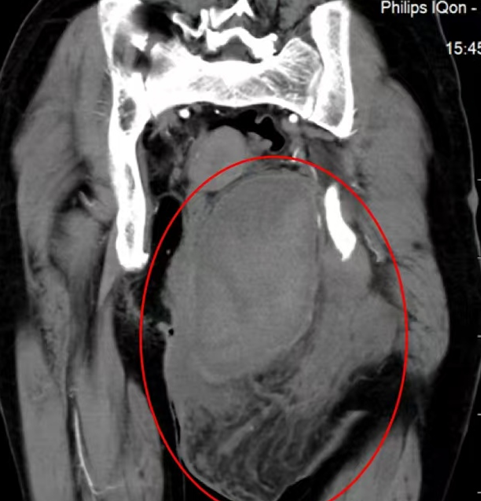

患者21岁女性,因左下腹隐痛2月,检查发现左腰骶椎前占位4天来诊。入院后进一步完善影像学检查提示左侧L5/S1椎间孔及椎体前后方占位。病灶钻缝生长,延伸至椎管内,再沿L5左侧横突孔向后伸至脊柱旁,横突孔增宽增大,骨质变薄,邻近肠管、左侧髂总血管稍推压移位。穿刺活检结果提示神经鞘瘤。

图片 7.png

图片 8.png